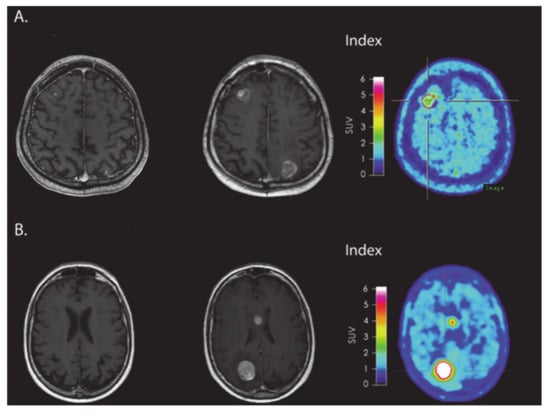

- Antonios, J.P.; Soto, H.; Everson, R.G.; Moughon, D.L.; Wang, A.C.; Orpilla, J.; Radu, C.; Ellingson, B.M.; Lee, J.T.; Cloughesy, T.; et al. Detection of immune responses after immunotherapy in glioblastoma using PET and MRI. Proc. Natl. Acad. Sci. USA 2017, 114, 10220–10225. [Google Scholar] [CrossRef]